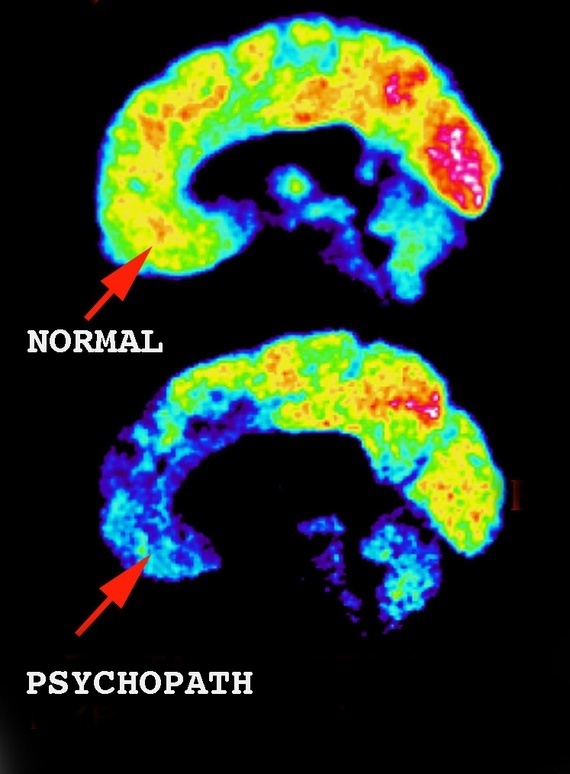

Education And Re Education In Youth The Extreme Importance Of Developing The Capacity To Feel Guilt And Shame In Adolescence On at least one occasion, his aunt woke up to find her toddler nephew placing knives near her sleeping form.